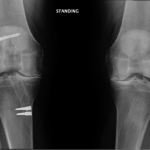

- A bow-legged knee deformity

Your doctor will diagnose osteoarthritis based on the medical history, physical examination, and X-rays.

X-rays typically show a narrowing of the joint space in the arthritic knee.